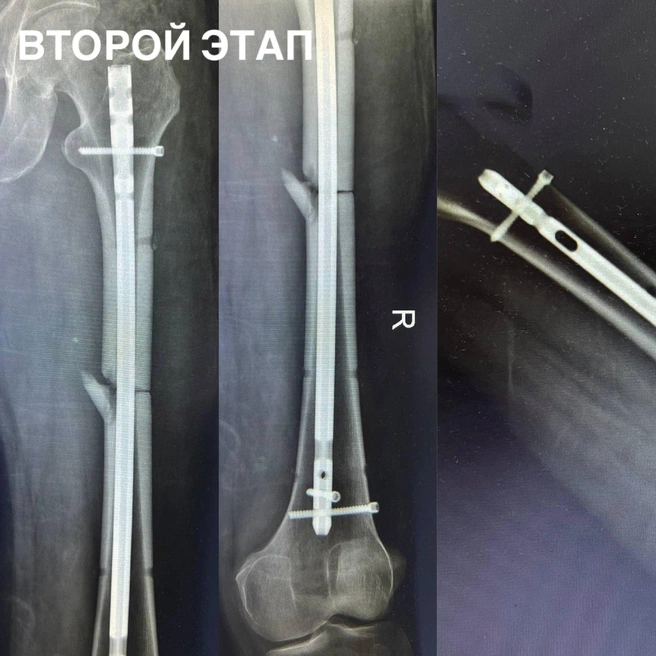

Пациент потерял много крови, но в считаные минуты команда травматологов стабилизировала состояние, обработала рану и подготовила пострадавшего к срочной операции. Медики провели интрамедуллярный блокируемый остеосинтез бедра — сложнейшую хирургическую методику, при которой внутри кости устанавливается металлический стержень.

Снимок рентген

Он удерживает раздробленные фрагменты, обеспечивая прочную фиксацию и возможность раннего восстановления. Операция длилась несколько часов и потребовала от врачей ювелирной точности и стальных нервов.